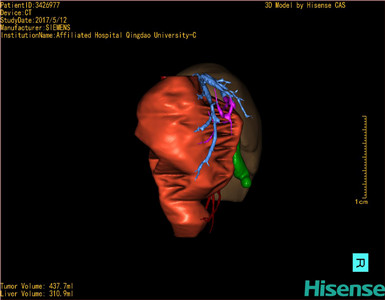

CT结果输入海信CAS系统后行3D重建及手术规划后,肿瘤位于右肾上腺区并周围淋巴结肿大,与血管关系紧密,建议化疗,静脉高营养、全量补液及对症支持治疗,患儿恢复良好,伤口无渗血渗液,无红肿疼痛,于2017-5-16出院。

术前三维重建:

重建图片